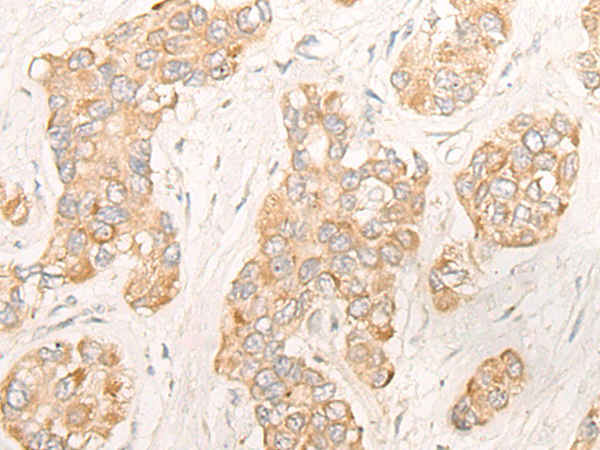

分类: 科研抗体货号: P06442别名: IL-34; C16orf77应用: WB,IHC反应种属: Human